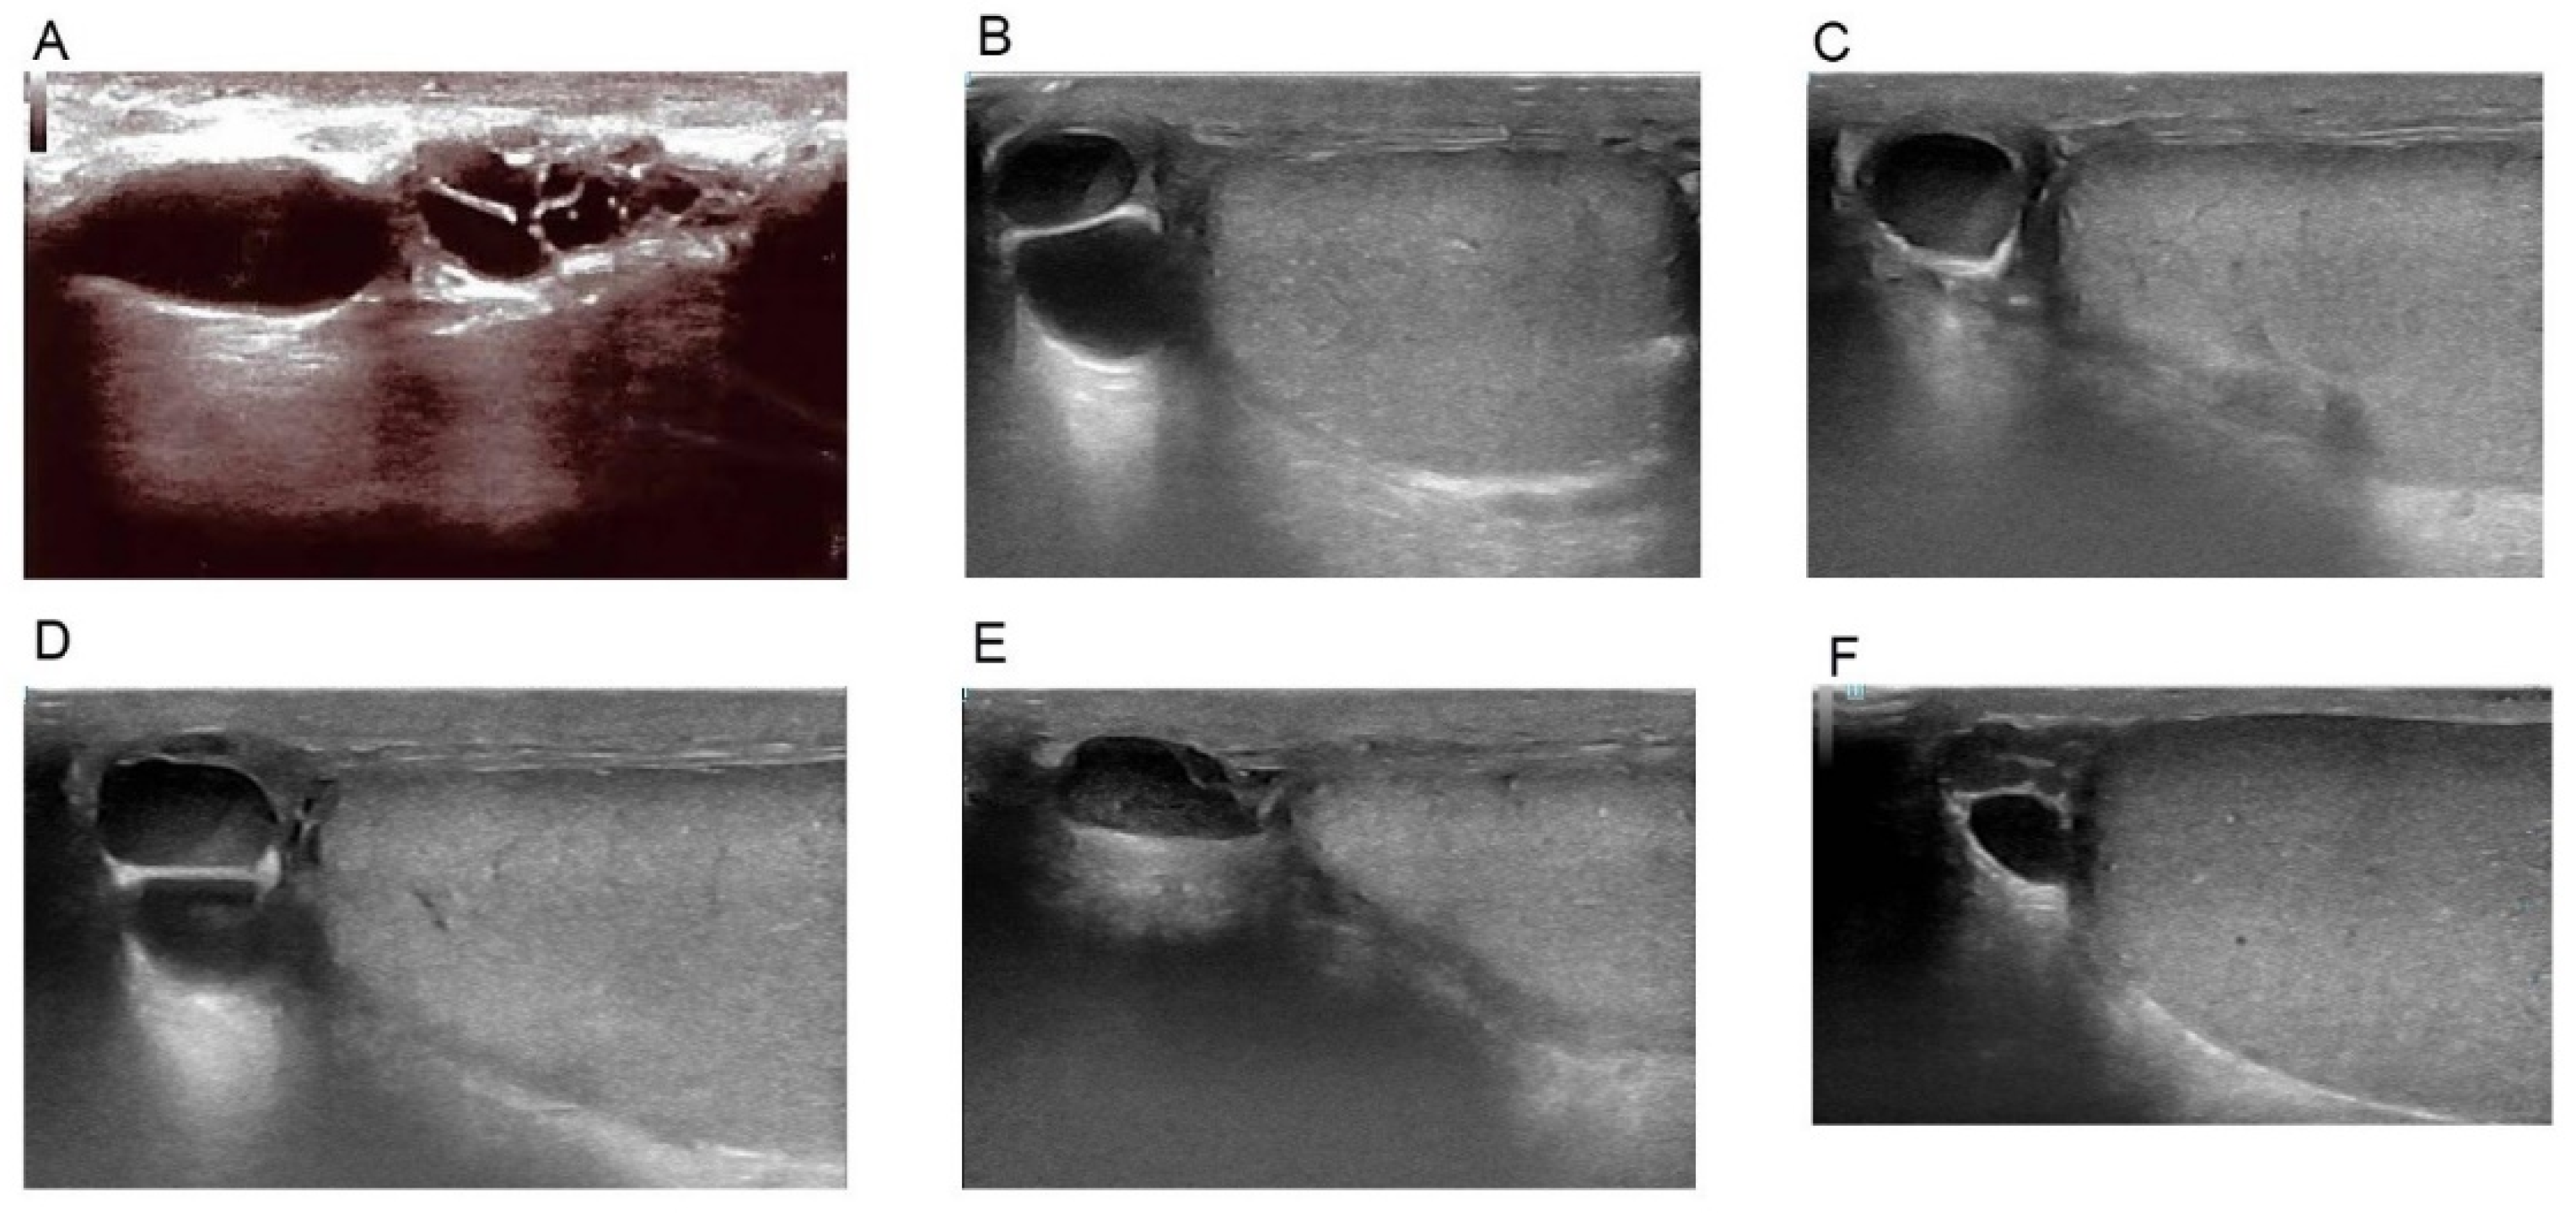

2. Materials and Methods

4. Discussion